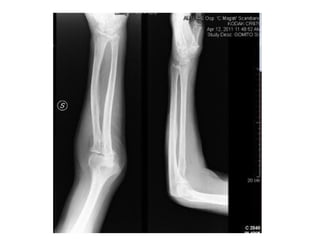

INCIDÊNCIAS COTOVELO

AP

PERFIL

• #5 3 razões: lembrar que a radiografia se dá em um único plano e, portanto, mais de um plano é importante para se ter certeza que a lesão existe ou não (já que esta pode aparecer em uma incidência, mas não na outra) e para determinar o alinhamento das fraturas. Aqui está o link para se falar de posicionamento

• #6 A mesma fratura. Uma vista em ap e outra em perfil. Isso mostra que a mesma imagem toma formas diferentes dependendo da incidência. Por isso é importante ter duas incidências no mínimo, pois elas se complementam